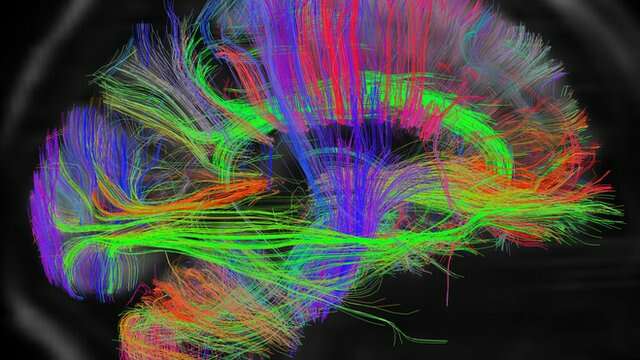

Usando una técnica llamada imagen por resonancia magnética funcional, los neurocientíficos pueden poner a alguien en un escáner y ver qué partes del cerebro se activan cuando hacen o piensan en algo.

Una simple acción, como cerrar y abrir el puño de la mano o decir unas pocas palabras requiere de la actividad de mucho más de una décima parte del cerebro. Incluso cuando se supone que no se está haciendo nada, el cerebro está haciendo mucho, ya sea controlando funciones como respirar y el palpitar del corazón, o recordando cosas por hacer. (1)

Incluso al dormir, el cerebro se mantiene activo, como muestra esta imagen de la actividad al soñar.

Incluso al dormir, el cerebro se mantiene activo, como muestra esta imagen de la actividad al soñar.